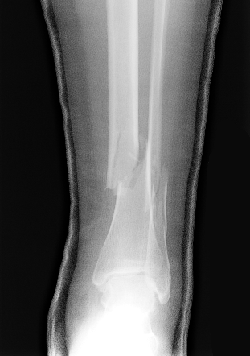

| Look at the radiographs below. Both images show a patient with a fracture of both the tibia and fibula. In this case, the fractures are laterally and anteriorly displaced. | |

AP View |